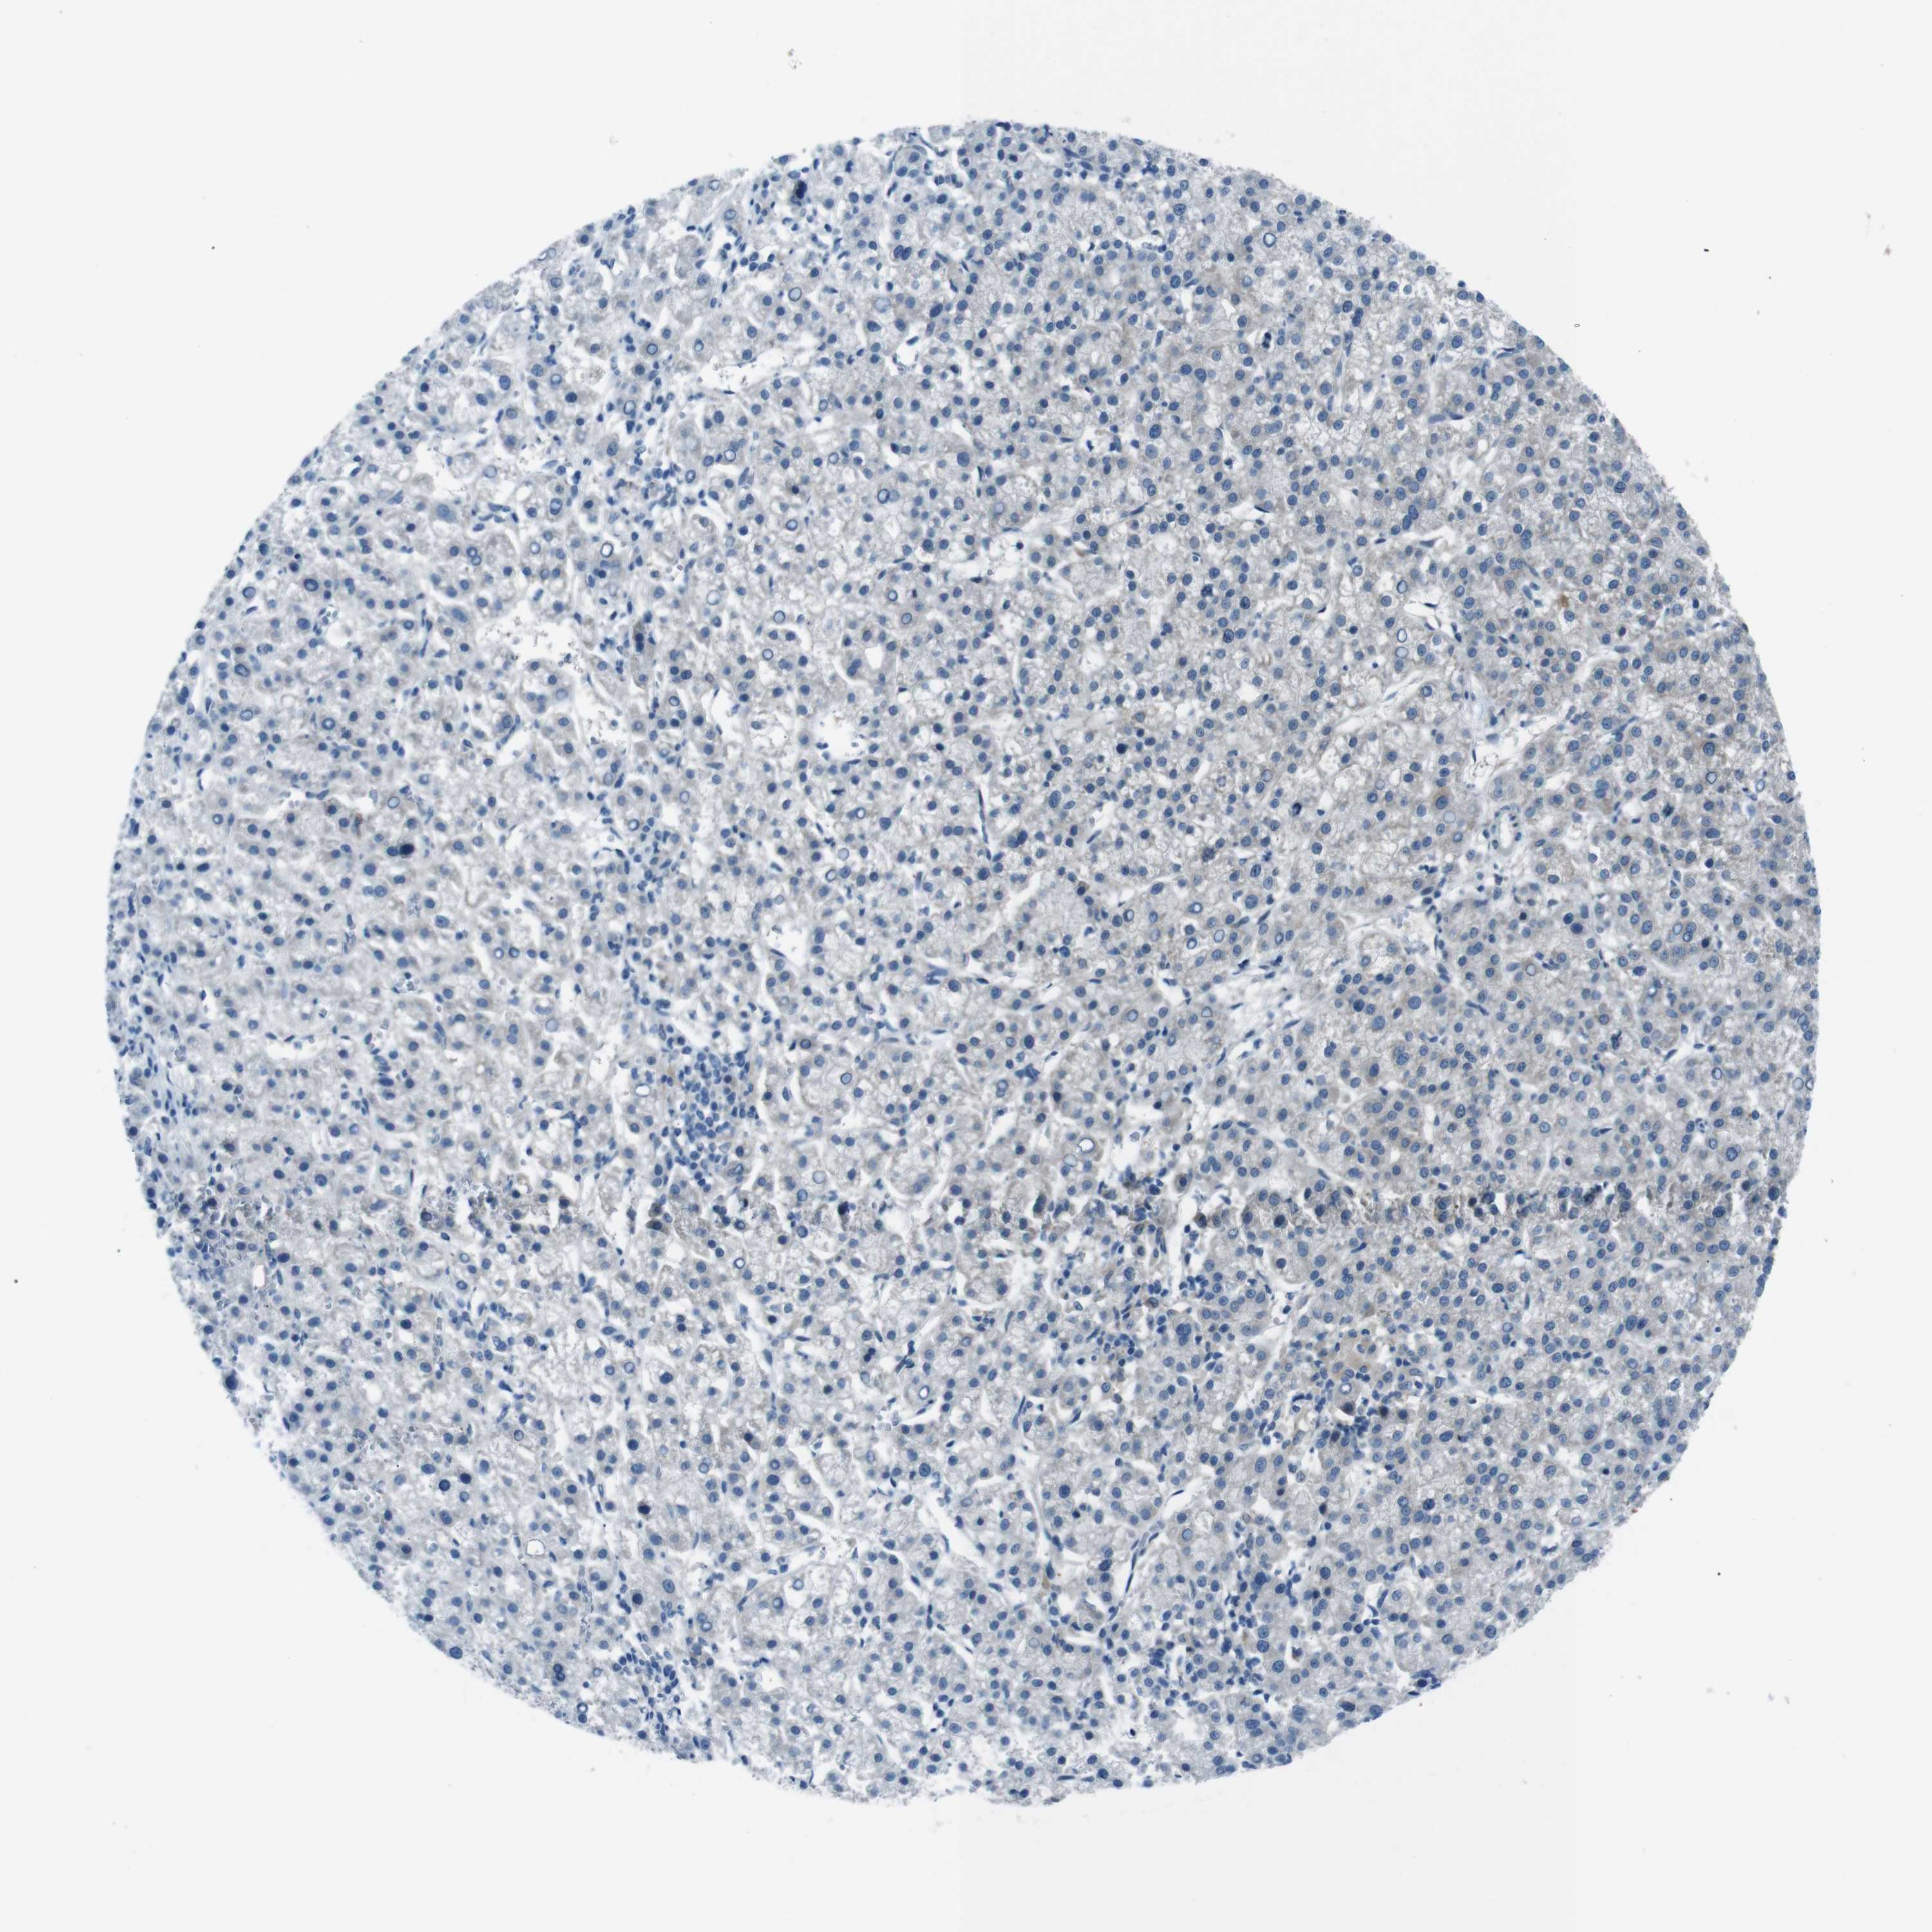

LIVER CANCER - Protein expressioni

A mouse-over function shows sample information and annotation data. Click on an image to view it in a full screen mode. Samples can be filtered based on level of antibody staining by selecting one or several of the following categories: high, medium, low and not detected. The assay and annotation is described here.

Antibody stainingi

Antibody staining in the annotated cell types in the current human tissue is reported as not detected, low, medium, or high, based on conventional immunohistochemistry profiling in selected tissues. This score is based on the combination of the staining intensity and fraction of stained cells.

Each image is clickable and will lead to virtual microscopy that enables deeper exploration of all samples and also displays staining intensity scores, fraction scores and subcellular localization as well as patient and tissue information for each sample.

Antibody HPA007293

Antibody CAB009771

Staining

High

Medium

Low

Not detected

Intensity

Strong

Moderate

Weak

Negative

Quantity

>75%

75%-25%

<25%

None

Location

Nuclear

Cytoplasmic/membranous

Cytoplasmic/membranous,nuclear

Cholangiocarcinoma

Carcinoma, Hepatocellular, NOS